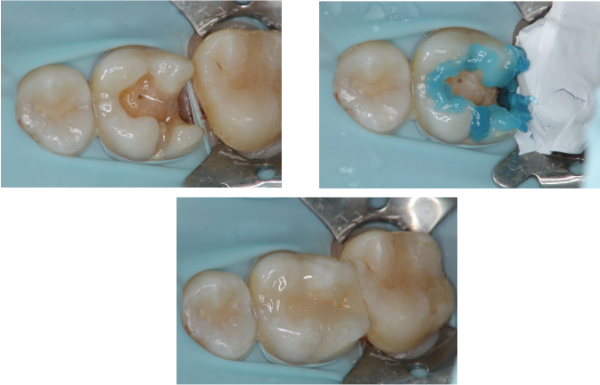

治療前,二次蛀牙

蛀牙未到牙髓

崁體製備,雷射牙齦修整

陶瓷崁體邊緣完整

無殘膠存在